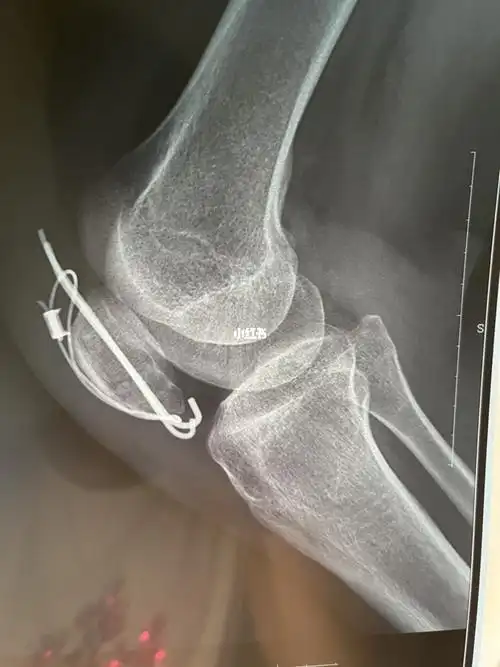

髌骨骨折第三十一天记录康复日记